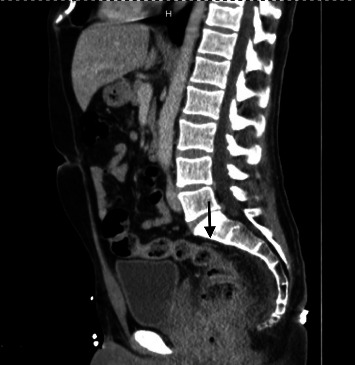

Prior to this hospitalization, the patient had recurrent episodes of bloody diarrhea at home for the last two weeks. Despite one-week tecovirimat (TPOXX) therapy, MPXV-induced proctitis progressed to severe rectal bleeding requiring transfusion. He had an episode of syncope and woke up on the bathroom floor covered in diarrhea and blood. Then, he called 911 (Universal Emergency Number) and was brought to the emergency department (ED). In ED, the patient was tachycardic and had a hemoglobin of 9.9 (103 g/µL) which was much lower than his baseline hemoglobin of 15.1 (103 g/µL) recorded two weeks ago. The patient's hemoglobin dropped further to 7.0 (103 g/µL) during this admission. CT angiography (CTA) abdomen and pelvis (Figure 2) revealed circumferential wall thickening with significant inflammatory changes at the level of the distal rectum and anus indicating proctocolitis. Two small, round hypodensities were observed near the distal rectum, with measurements of 11 mm and 14 mm. These findings raised suspicion of rectal abscesses.

Figure 2.

CT angiography (CTA) of the abdomen and pelvis. CT angiography revealed circumferential wall thickening with significant inflammatory changes at the level of the distal rectum and anus, indicating proctocolitis (black arrow). Small rounded hypodensities, adjacent to the distal rectum measuring 11 and 14 mm, were suspicious for rectal abscesses.